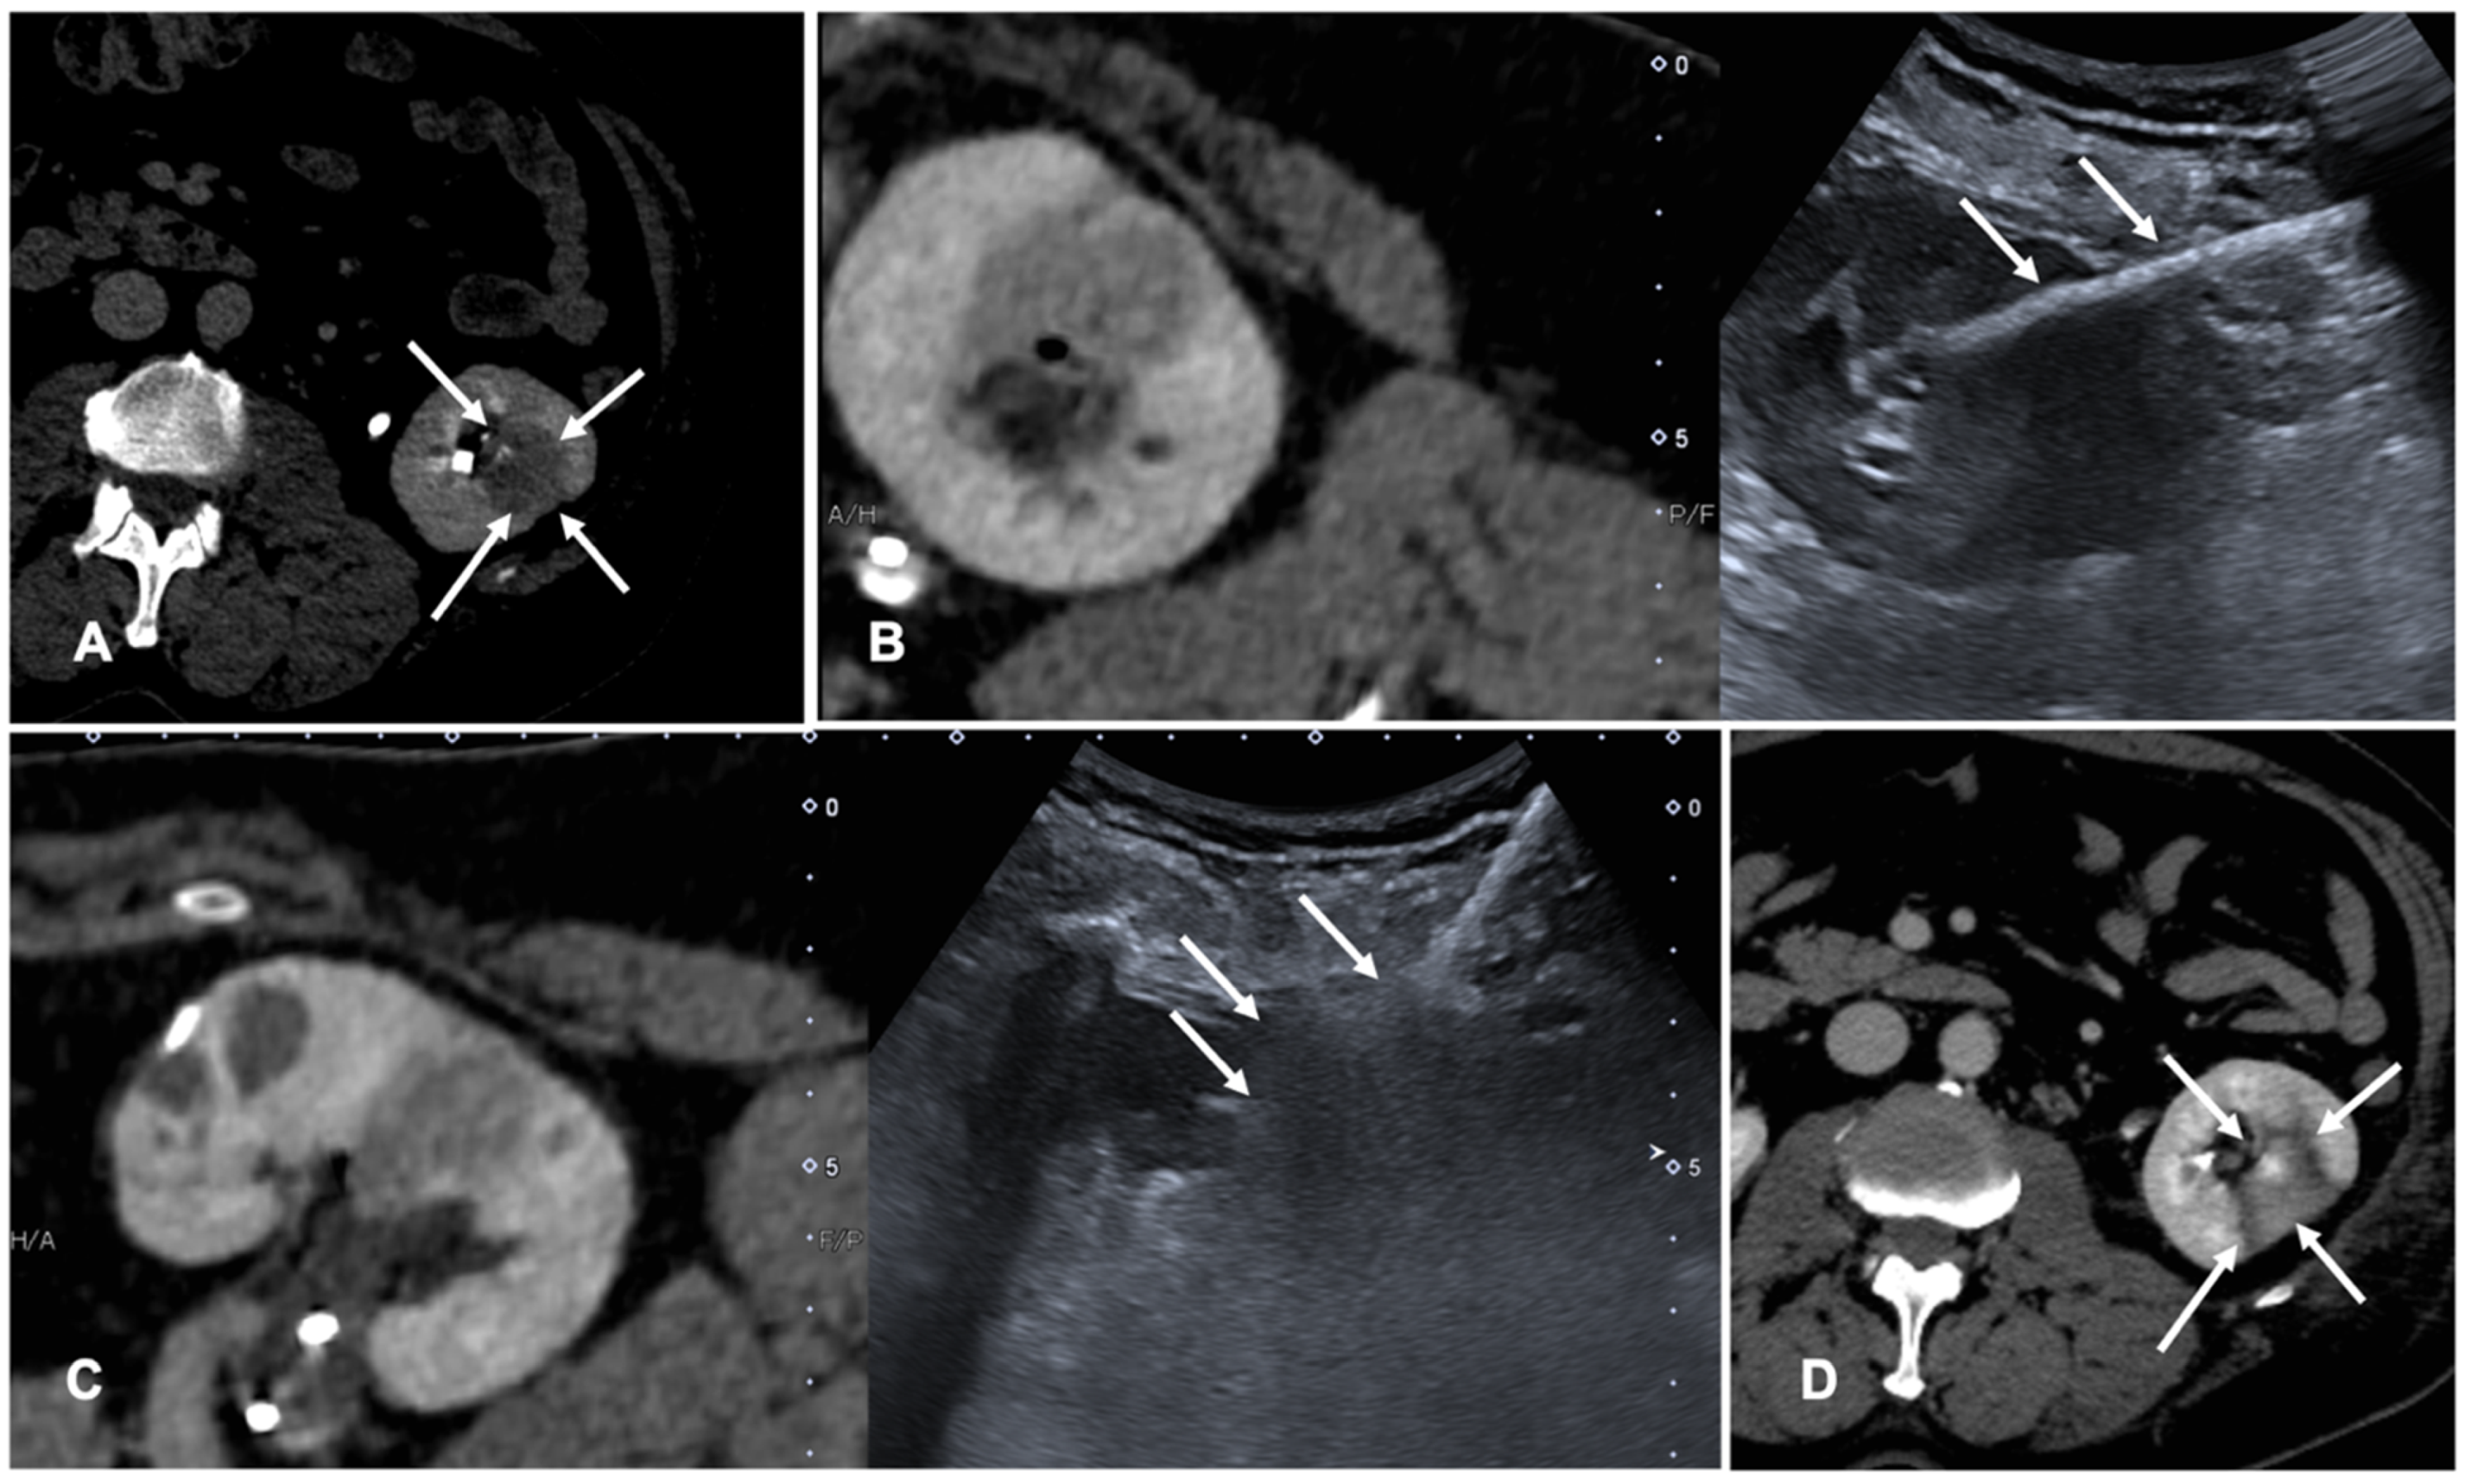

FI is used to co-register previous CT or CBCT and real-time US to perform tumor ablations. Assisted CBCT and US FI are effective, safe and feasible in TA, but only a few papers investigated the advantages and limitations of these techniques [35,36,37]. A case of a patient with renal tumor treated with the guidance of FI is shown in Figure 3.

Figure 3. Case of a patient with left kidney clear cell renal cancer treated with microwave ablation (MWA). (A) Axial view during delayed excretory phase of the preoperative contrast enhanced Computed Tomography (CECT) showing a 25 mm intrarenal lesion (white arrows); (B) Fusion imaging (FI) of the same CT (left side) and intraoperative ultrasound (right side). MWA needle is marked by two solid arrows on the right. (C) FI during MWA of the lesion. Arrows point out the area of gas formation at the tip of the ablation needle. (D) An axial view of the control CT at the end of the procedure. Arrows point out the resulting completely ablated area of the kidney lesion.